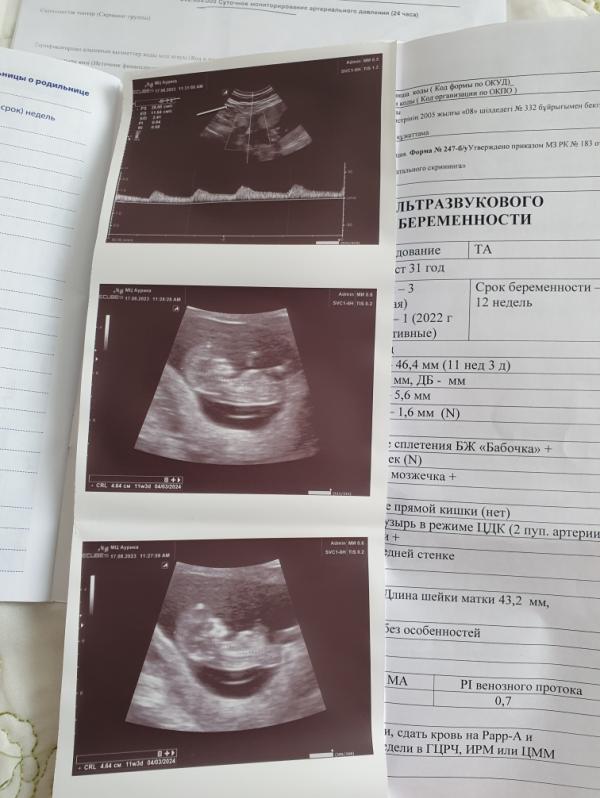

У нас вот такие вот Пироги) точнее пирожочек🥰 снова все по новой, но я безумно рада))) жизнь идёт по плану Всевышнего😇 Альхамдуллилях, мои желания с этим планом совпадают 🙏🏻🙏🏻🙏🏻